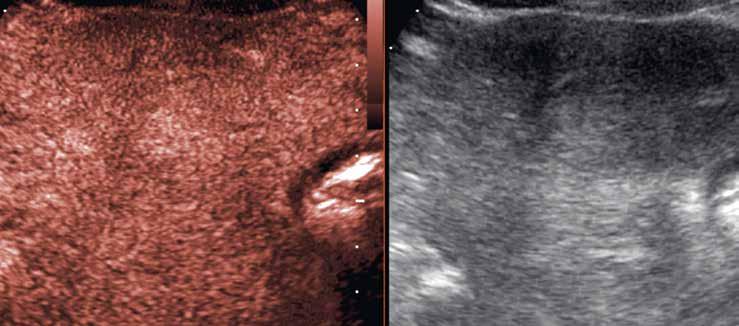

V UZ jsou patrná vícečetná izoechogenní ložiska (1, 2). U jiného pacienta (3) vidíme v játrech převážně hypoechogenní ložiska (žluté šipky) s naznačeným hyperechogenním periferním lemem (červené šipky). Po aplikaci kontrastní látky se ložiska patrná na obr. 1, 2 homogenně sytí a ani téměř po třech minutách nedochází k jejich vymývání (4–6).

Již nativně jsou na T1-váženém obraze vidět vícečetná hyperintenzní ložiska (7). V arteriální fázi ložiska zůstávají hyperintenzní (8), v portovenózní fázi (9) a v hepatospecifické fázi (10) postupně splývají s okolním parenchymem.